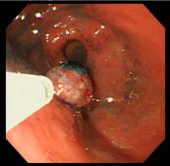

| 切除した部分をクリップで止血 | ポリープ切除した部分の1ヶ月後の粘膜 | ||